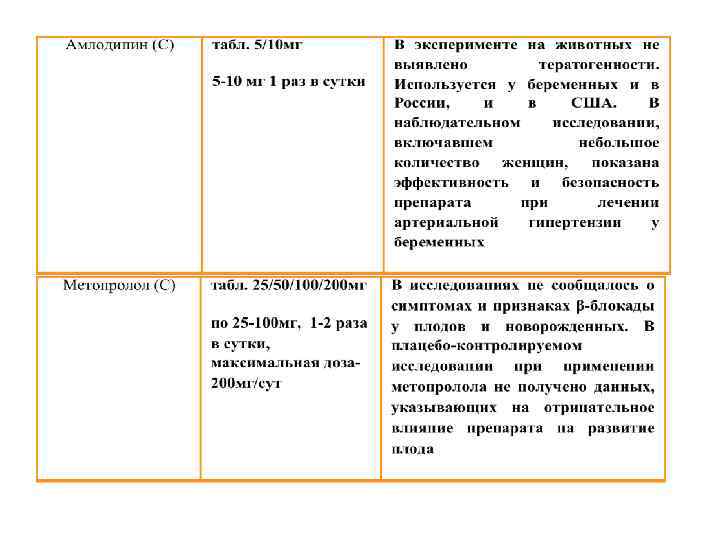

АГ ПРИ БЕРЕМЕННОСТИ Антигипертензивные препараты, применяемые для лечения АГ в период беременности

АГ ПРИ БЕРЕМЕННОСТИ Антигипертензивные препараты, применяемые для лечения АГ в период беременности